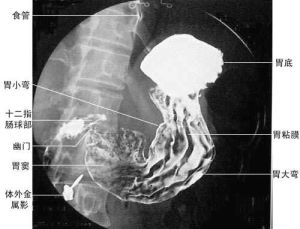

鋇餐造影——即上消化道鋇劑造影檢查,是讓受檢者吞食糊狀硫酸鋇(顯影劑)後,通過鋇劑在經食道到達胃、十二指腸部位的顯影過程來進行上消化道疾病的診斷方法,因為它不溶於水和脂質,所以不會被胃腸道黏膜吸收,因此對人基本無毒性。鋇餐造影即消化道鋇劑造影,是指用硫酸鋇作為造影劑,在X線照射下顯示消化道有無病變的一種檢查方法。

鋇餐造影x線造影檢查使用得較多的是胃腸鋇餐造影和鋇劑灌腸造影。這項檢查安全、無創傷,無副作用,但有些患者,如急性呼吸道感染病人,嚴重心、肝、腎功能不全病人,以及碘試驗陽性的病人,一般不適宜做這項檢查。